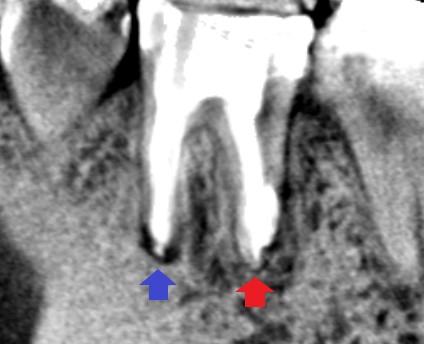

初診時の下顎第一大臼歯の矢状断のCT画像です。近心根と遠心根の根の先に膿の影がみられます。

矢印の先に膿の影がそれぞれみられますが、特に赤い矢印の先の遠心根の影が大きく、手術で根の先を半分切り残しているように見えます。